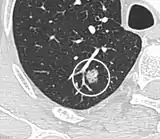

Round well-delineated solid lung nodule with smooth border.[9]